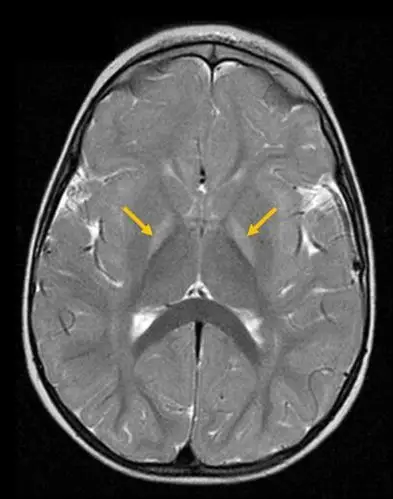

胆红素脑病的mri诊断

胆红素脑病,t2及flar高兴号

基底节区高信号提示胆红素血症对中枢神经系统的毒性作用是不可逆的.